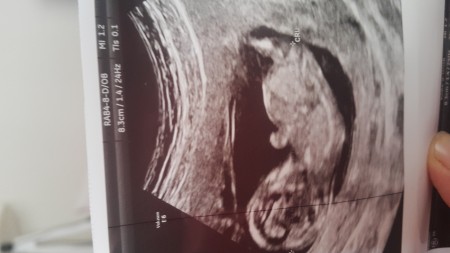

cinsiyet tahmini

Kaç haftalık canm ben kıza benzettim pek eli kolu daha ayrılmamış gibi geldi bana :)

13 haftalik daha

Küçük işte canm erkek bebek daha çabuk ellenir kollanir derlerde ne kadar doğru blmiyorum :) gönlündeki olsun inşallah

Bana da kız gibi geldi

Bence erkek canım öyle tahmin ettim:)

13 haftalik da %70 olarak cinsiyetin tahmin etmesi doğrumu doktorun haftaya göre tahminde bulunması tuah geldi bana

Canım 11. Haftada söyleyeni duydum ben